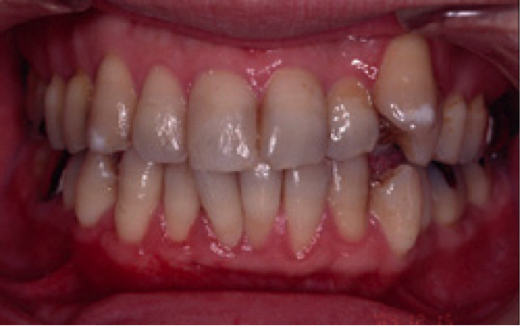

【男性(初診時38歳)非喫煙者】

歯肉が全体的に下がっていることを主訴に来院されました。特にひどいのが右下の犬歯付近で、ここについては手術を受けてでも治したいとのことでした。このような状態を歯肉退縮と呼びますが、原因は大きく分けて二つ考えられます。一つは強く歯を磨きすぎること、もう一つは歯ぎしりなどの噛み合わせの不具合です。必ず事前の診査により原因を除去しておかないと、手術をして元通りになったとしても、またすぐに下がってしまいます。この症例では口蓋より結合組織を採取し、右下犬歯の部分に移植しました。